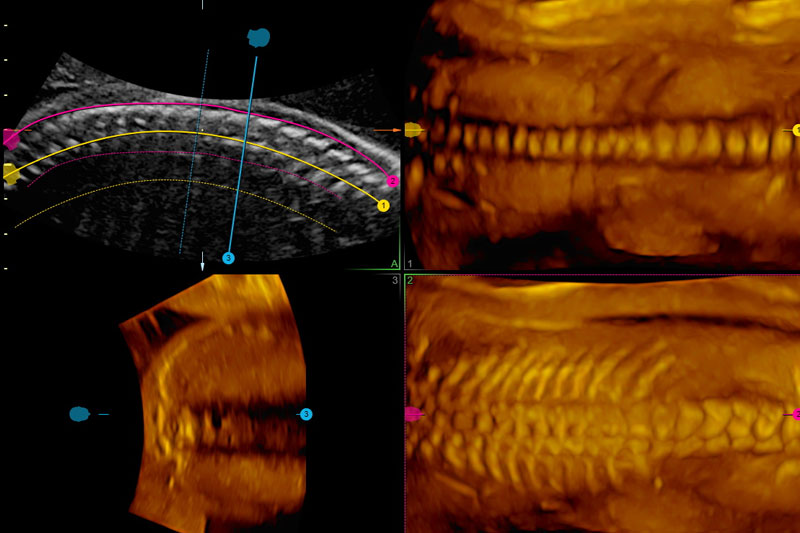

FMF-certified scanning protocols, high-resolution ultrasound, and global screening standards.